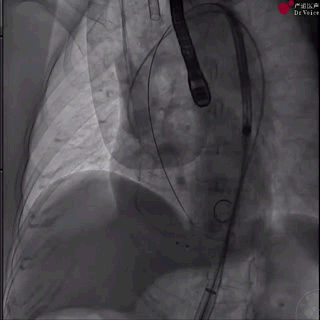

1、从左侧股动脉完成主动脉瓣根部造影,结果提示主动脉瓣大量反流;

主动脉根部造影